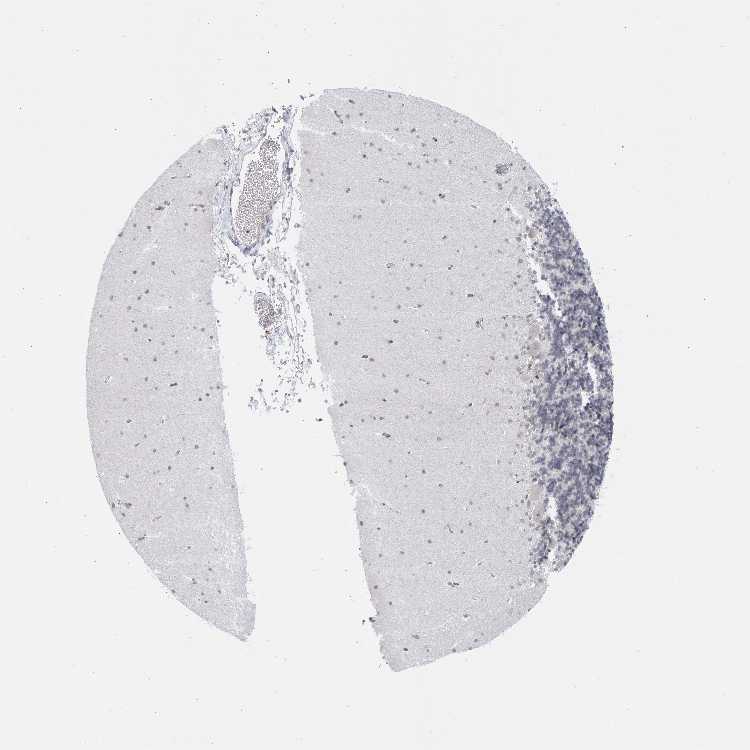

CEREBELLUM - Antibody stainingi

Antibody staining in the annotated cell types in the current human tissue is reported as not detected, low, medium, or high, based on conventional immunohistochemistry profiling in selected tissues. This score is based on the combination of the staining intensity and fraction of stained cells.

Each image is clickable and will lead to virtual microscopy that enables deeper exploration of all samples and also displays staining intensity scores, fraction scores and subcellular localization as well as patient and tissue information for each sample.

Antibody HPA028088Antibody HPA028631Antibody HPA030086

Purkinje cells Not detectedNot detectedLow

Cells in granular layer Not detectedNot detectedMedium

Cells in molecular layer Not detectedLowLow